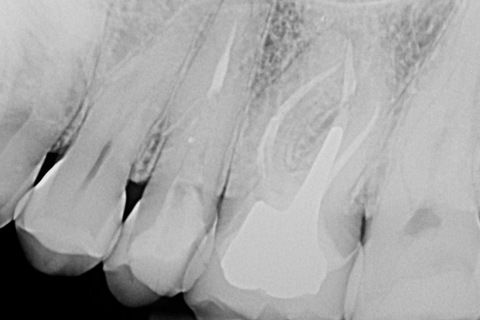

Paciente sexo feminino indicado ao consultório para avaliação e tratamento de perfuração recente , sem presença de lesão, realizada durante a cirurgia de acesso em dente 26. Rx inicial.